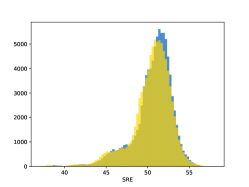

To visualise similarity metrics that compare image pairs (RMSE, SRE, SSIM) two metric distributions are generated: intra-similarity and inter-similarity. For each compared sample 300 random images are selected. The inter-similarity distribution is calculated for each image pair combination from both compared samples e.g. generated images of COVID-19 and real images of COVID-19. For the intra-similarity, all pairs of images in a single sample e.g real images of COVID-19 are considered. By comparing the shape of intra-similarity for the training subsample (Dataset) with the inter-similarity of training and generated samples the quality of the generated sample can be judged. It is also possible to compare in this way between the four image classes present in the dataset. The resulting distributions of inter-similarity of COVID-19 and the three remaining classes are compared in Fig. 4 to distributions of intra-similarity of the COVID-19 sample for each metric. All metrics, as expected based on available medical evidence Rubin et al. (2020), indicate that there are visible differences not only between COVID-19 and normal samples but also between viral pneumonia and lung opacity. Therefore, all classes should be distinguishable.

To visualise differences between synthetic and real samples distributions are generated for each of the RMSE, SRE and SSIM metrics: intra-similarity and inter-similarity. For each compared sample 300 random images are selected. The inter-similarity distribution is calculated for each image pair combination from both compared samples e.g. generated images of COVID-19 and real images of COVID-19. For the intra-similarity, all pairs of images in a single sample e.g real images of COVID-19 are considered. The distributions for generated samples describe very well the distributions for corresponding real images as shown in Fig. 6.